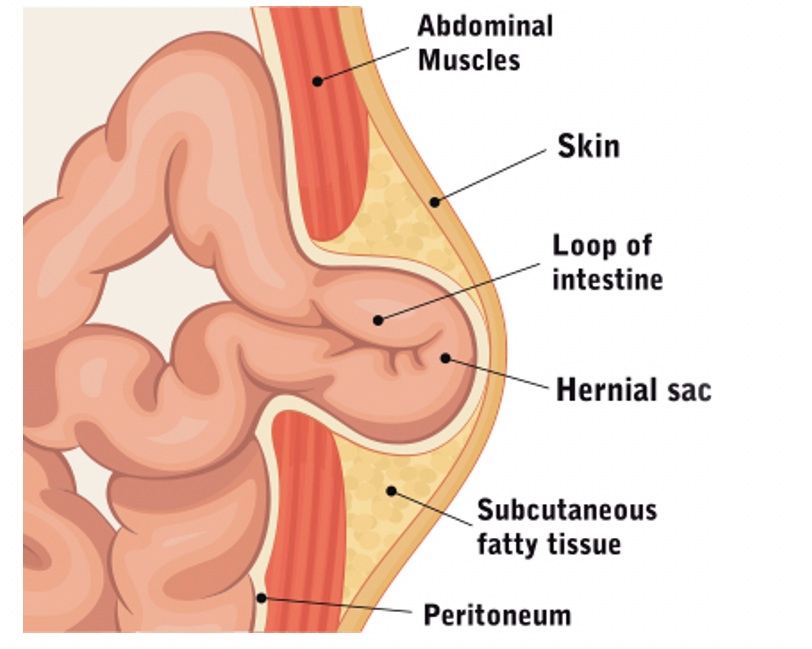

A hernia occurs when an internal organ pushes through a weak spot in the muscle wall, causing a visible bulge and discomfort.

A visible or noticeable bulge in the abdomen or groin often indicates a hernia and should be examined by a surgeon to avoid pain, complications, or enlargement.